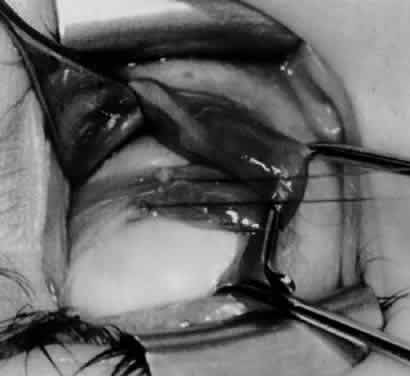

Fig. 13. The inferior oblique muscle is sectioned from the globe. A preplaced 6-0 Vicryl suture is attached to the insertion.

Fig. 14. The inferior temporal vortex vein, 8 mm posterior to the temporal insertion of the inferior rectus muscle, is held on a Green muscle hook.